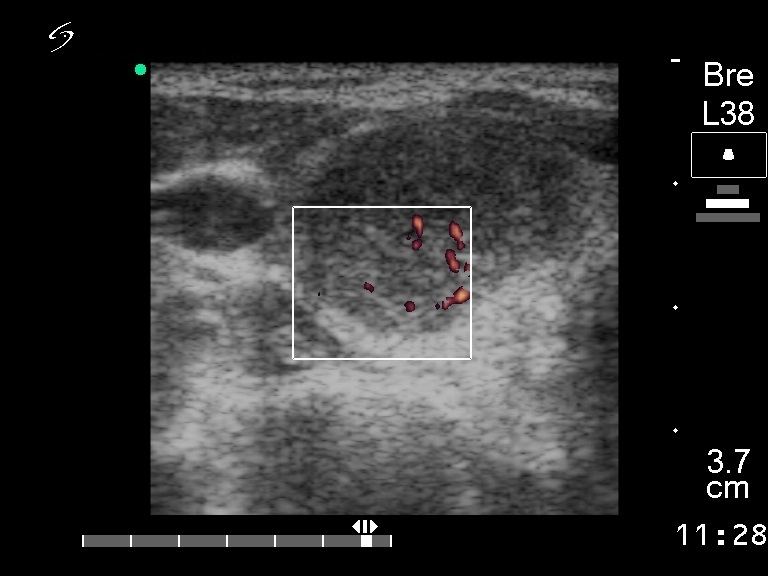

Ultrasonography: a solitary hypoechogenic nodule in the right lobe with a halo sign and perinodular blood flow.